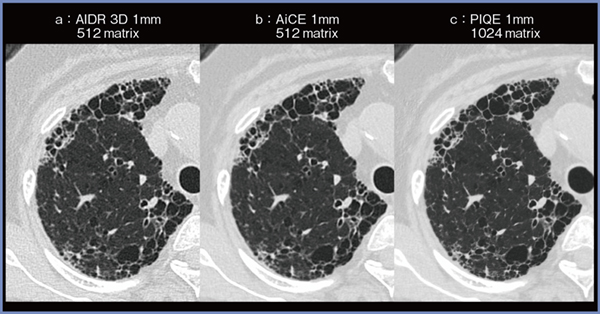

症例1(図1)は80歳代,女性,慢性線維化性間質性肺炎症例で,Hybrid IRの「Adaptive Iterative Dose Reduction 3D(AIDR 3D)」(a),Deep Learning Reconstruction(DLR)の「Advanced intelligent Clear-IQ Engine(AiCE)」(b),PIQE(c)の,それぞれスライス厚1mmの画像を比較している。PIQEにて最もノイズが低減されており,上葉の軽微な気腫性変化や胸膜直下の網状影がより明瞭である。当院ではZ軸の分解能を上げるために,スライス厚0.5mmにSR処理をかけている〔以下,0.5mm(SR)〕。PIQEと組み合わせることで,図2 a上段のように低ノイズの高解像度画像が得られ,蜂巣肺や牽引性気管支拡張,肺野の気腫性変化も明瞭に描出されている。肺底部レベルの画像(図2 a下段)では,右肺底部の蜂巣肺内にfungus ballを認めた。また,当院では,びまん性肺疾患の病変分布や経時的変化の評価にMPRを利用しているが,図2 b,cはノイズが少なく,下肺野優位の蜂巣肺や網状影,上肺野優位の気腫性変化が明瞭に描出されている。

図1 症例1:慢性線維化性間質性肺炎